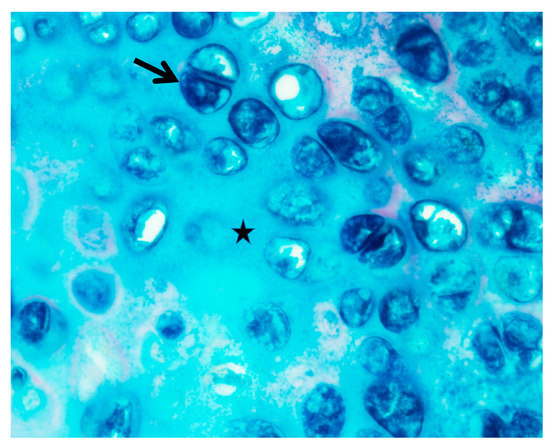

| Pathology (Colloidal iron stain) | – | Not tested | Tonsils (+) Adenoids (+) | Adenoids (–) | Tonsils (–) Adenoids (–) | – | Tonsils (+) Adenoids (–) | Trachea (+) Arytenoid (–) Tonsil (+) | Deep neck soft tissue (–) Trachea (+) | Arytenoid (+) Cricoid (+) | – | – | – | – | – | ||

| Pathology (Colloid iron stain) | |

| Tonsil | 3/5 (60.0) |

| Adenoid | 1/6 (16.7) |

| LM | 1/5 (20.0) |

| Neck | 0/3 (0.0) |

| Trachea | 2/3 (66.7) |

| Cricoid | 1/3 (33.3) |